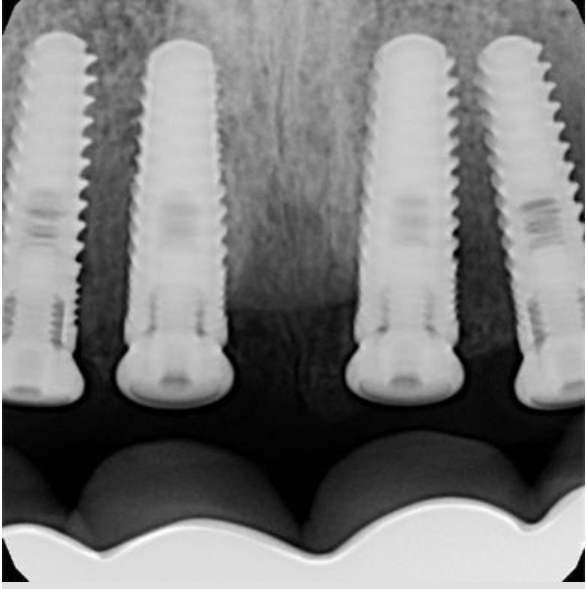

Case 5

Implant ball-snaps help to hold the denture in place

Dentures snapped in place